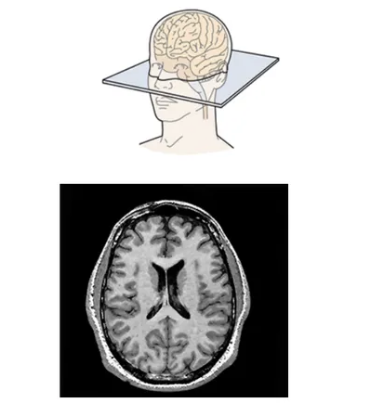

horizontal plane

knowt flashcard image